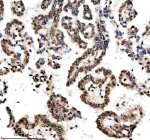

Immunohistochemical staining of Histone H3 (acetyl K9) using anti-Histone H3 (acetyl K9) antibody. Histone H3 (acetyl K9) was detected in a paraffin-embedded section of human breast cancer tissue. Heat mediated antigen retrieval was performed in EDTA buffer (pH 8.0, epitope retrieval solution). The tissue section was blocked with 10% goat serum. The tissue section was then incubated with a dilution of 1:50 rabbit anti-Histone H3 (acetyl K9) antibody overnight at 4oC. Peroxidase Conjugated Goat Anti-rabbit IgG was used as secondary antibody and incubated for 30 minutes at 37oC. The tissue section was developed using an HRP secondary and DAB substrate.